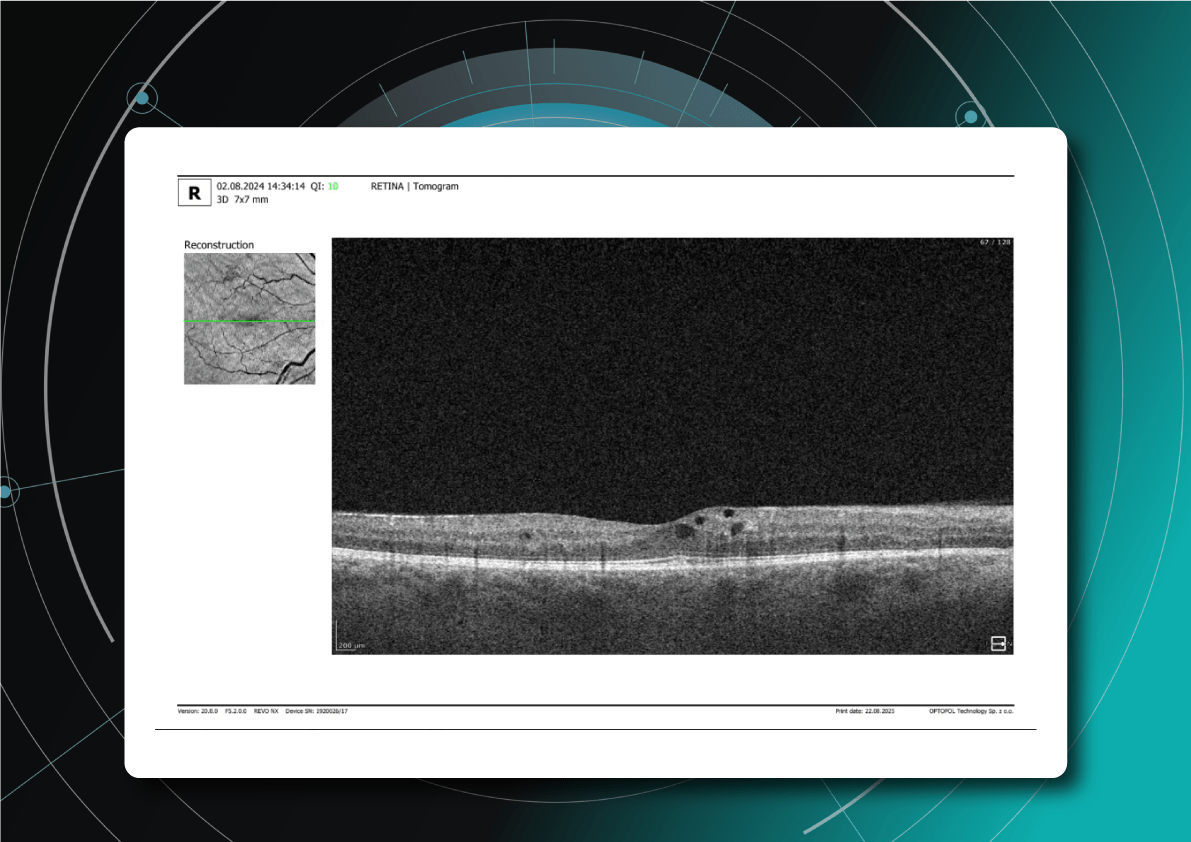

How does the standard report look?

OCT has become a golden standard for diagnosing and monitoring many ocular pathologies, thanks to its unparalleled level of detail in ophthalmic imaging.

While retinal reports vary among OCT models, they typically include:- a foveally centered B-scan,

- a quantitative thickness map,

- and a semi-quantitative thickness map.

The B-scan offers a visual snapshot of foveal architecture and confirms proper scan centering. The quantitative thickness map employs the ETDRS sector map to measure retinal thickness within a 6mm circle around the fovea, with specific measurements for the foveal sector (1mm), inner macular ring (3mm), and outer macular ring (6mm).

Progression analytics enable comparison of serial macular scans, which is invaluable for managing vitreomacular interface disorders and macular edema. The semi-quantitative thickness map provides a broader overview of retinal thickness throughout the scan.

Given this amount of data, it is challenging to identify subtle and localized retinal pathological changes. As a result, entire OCT datasets are represented by few aggregated values, and the standard OCT reports generated by most devices often rely on significant data reduction to simplify interpretation, which you can usually not customize.